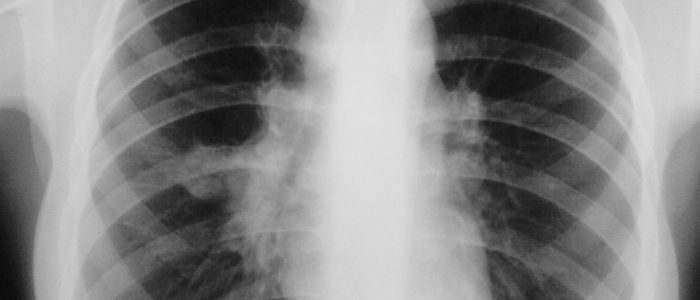

Если гемангиома располагается на коже груди, то ее замечают, когда проводят внешний осмотр пациента. У детей она появляется через несколько дней после рождения. Врач предварительно ставит диагноз и для подтверждения проводится дополнительное обследование, которое включает:

- ультразвуковое исследование ― для определения насколько опухоль обширна и, глубоко ли лежит.

- ангиография ― проводится при наличии нескольких пятен или поражении органов проводят.